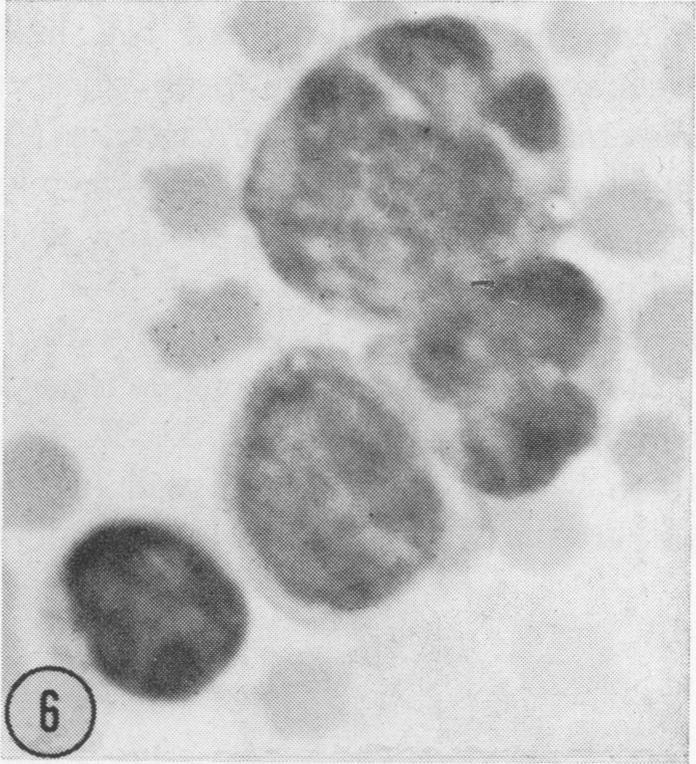

CYTOLOGICAL OBSERVATIONS ON A BOVINE LYMPHOSARCOMA.

Nature. 1964 Jan 25;201:368-71. doi: 10.1038/201368a0.